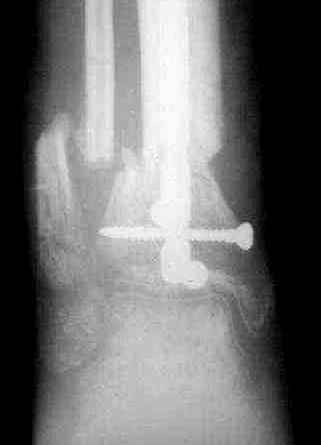

5, 6 - через 2,5 мес после травмы выполнен закрытый остеосинтез блокируемым штифтом.

7, 8, 9, 10, 11 - через 8 мес после травмы перелом сросся.